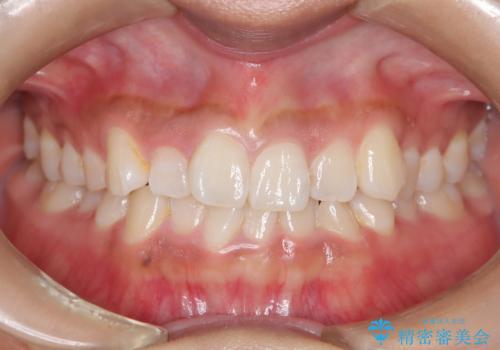

[ 前歯のねじれ・がたつき ] マウスピース矯正

![[ 前歯のねじれ・がたつき ] マウスピース矯正の症例 治療前](https://seimitsushinbi.jp/wp/wp-content/uploads/2024/02/4007c6479f6bce11863dcdd32ed5e39b-500x350.jpg?v=1708502552)

![[ 前歯のねじれ・がたつき ] マウスピース矯正の症例 治療後](https://seimitsushinbi.jp/wp/wp-content/uploads/2024/02/e7a01485e4f4dd0da04705fde4cc34cc-500x350.jpg?v=1708502585)